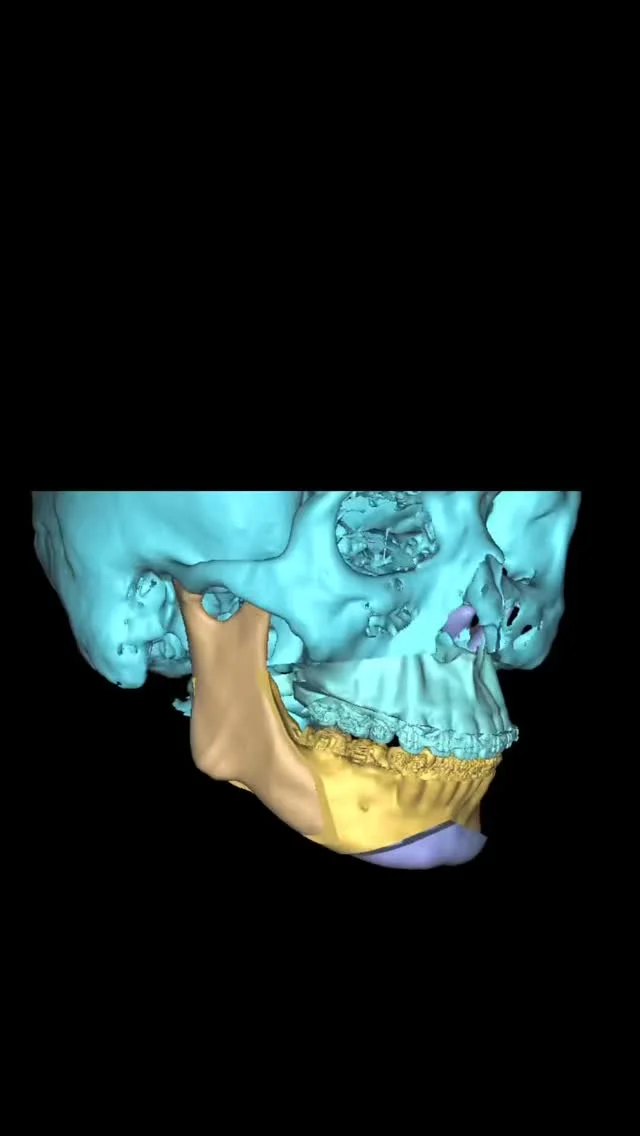

大学病院や総合病院で長年、親知らず抜歯や歯根端切除術などの小手術から、全身麻酔下で行う顎矯正手術(骨切り)、口腔腫瘍、インプラント治療など幅広い口腔外科診療・手術に携わってきました。

これまでに数多くの難症例を担当し、「安全、スピーディーかつ合併症を低減する手術」を常に意識してきました。特に骨切り手術では、機能面の改善だけでなく、顔貌のバランスや審美性にも配慮し、口元の自然な美しさを追求しています。

日本口腔外科学会専門医、日本顎変形症学会認定医など、多くの専門資格を有し、先端の知見と技術に基づいた治療を提供します。